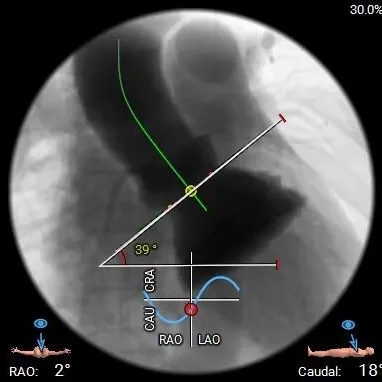

术前CT分析

主动脉根部测量

Annulus

24.5mm

LVOT

30.8mm

水平夹角

39°